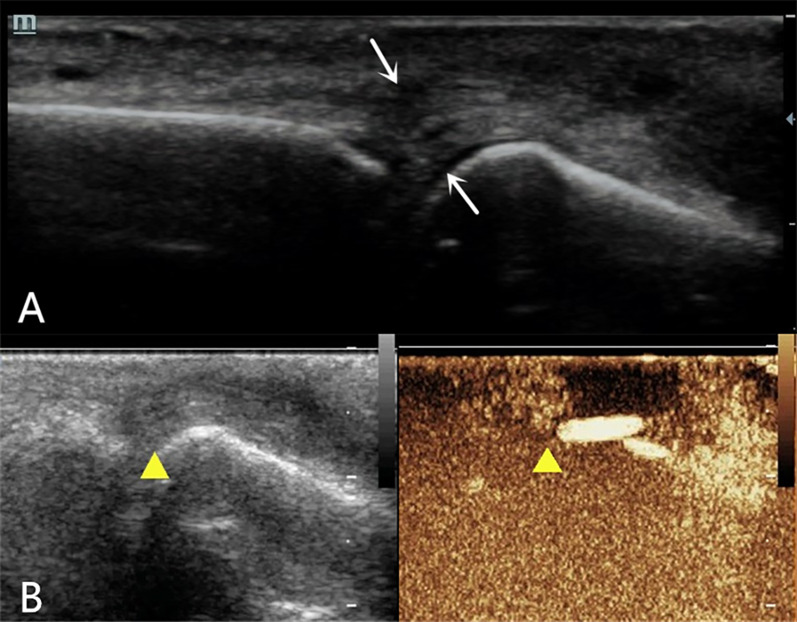

Background: By combining high-frequency and contrast-enhanced ultrasound (CEUS), the position of the severed end of a finger extensor tendon injury and the injury classification can be determined as part of a comprehensive preoperative evaluation in clinical practice. However, there have been no reports of high-frequency ultrasound combined with CEUS for the preoperative diagnosis of human finger extensor tendon injury.

Cases presentation: One case of complete rupture of the extensor tendon was diagnosed by ultrasound, which was completely consistent with the surgery; one case of incomplete rupture was ultimately confirmed clinically; and one case of distal phalangeal bone base avulsion fracture with tendon contusion and missed diagnosis on the first radiographic examination was confirmed by follow-up radiographic examination.

Conclusions: Different types of finger extensor tendon injuries exhibit distinctive contrast-enhanced ultrasonography findings. Combined high-frequency and contrast-enhanced ultrasound can accurately locate the position of the severed end of the finger extensor tendon injury before surgery while observing the contrast agent filling area to clarify injury classification, providing a reliable imaging basis for clinical practice and ultimately developing personalized diagnosis and treatment plans for patients to ensure minimal trauma and pain, as well as optimal treatment effects.